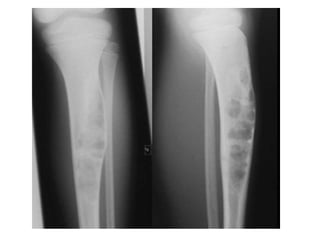

OSTEOFIBROUS DYSPLASIA

• Osteofibrous dysplasia (OFD) is a benign, non-osseous

lesion of bone typically seen in the anterior cortex of

the tibia, particularly in children or teenagers.

• It is commonly seen in children in the first decade and

can on rare occasions be polyostotic.

• It is almost exclusively seen in the tibia but can on rare

occasion affect the ipsilateral fibula or be bilateral at

presentation.

• It presents with moderate expansion of bone which is

manifest as a palpable lump or progressive bowing of

the tibia.

• It is usually painless but stress fractures and

pathological fractures can occur.

• The lesion classically presents radiographically as

intracortical osteolysis, most commonly affecting the

anterior cortex of the tibia (Figure 9.23).

• There is expansion of the cortex to accommodate the lesion

which typically has a soap bubble appearance.

• There is a narrow zone of transition between the lesion and

normal bone with a surrounding rim of sclerotic bone on

the medullary side, which may obscure the medullary

canal.

• MRI demonstrates a cortical lesion with a surrounding area

of sclerosis which demarcate the lesion from its

comparable malignant variant, adamantinoma, which

typically demonstrates a ‘moth-eaten’ margin with

medullary involvement.

OSTEOFIBROUS DYSPLASIA • Osteofibrousdysplasia (OFD) is a benign, non-osseous lesion of bone typically seen in the anterior cortex of the tibia, particularly in children or teenagers. • It is commonly seen in children in the first decade and can on rare occasions be polyostotic. • It is almost exclusively seen in the tibia but can on rare occasion affect the ipsilateral fibula or be bilateral at presentation. • It presents with moderate expansion of bone which is manifest as a palpable lump or progressive bowing of the tibia. • It is usually painless but stress fractures and pathological fractures can occur.

• 34.

• The lesionclassically presents radiographically as intracortical osteolysis, most commonly affecting the anterior cortex of the tibia (Figure 9.23). • There is expansion of the cortex to accommodate the lesion which typically has a soap bubble appearance. • There is a narrow zone of transition between the lesion and normal bone with a surrounding rim of sclerotic bone on the medullary side, which may obscure the medullary canal. • MRI demonstrates a cortical lesion with a surrounding area of sclerosis which demarcate the lesion from its comparable malignant variant, adamantinoma, which typically demonstrates a ‘moth-eaten’ margin with medullary involvement. • Histologically, osteofibrous dysplasia appears as irregular fragments of woven bone rimmed by layers of lamellar bone laid down by osteoblasts.

• 35.

• The fibrouscomponent consists of bland spindle cells with collagen production and a matrix that may be myxoid or fibrous. • The histological appearance can be differentiated from fibrous dysplasia by the absence of keratin-positive epithelial cells in OFD, and from adamantinoma by the absence of epithelial cell clusters. • These three comparable lesions behave very differently in their natural history, however: OFD tends to progress through the first decade of life, stabilizing during the second and often healing or resolving spontaneously thereafter. • Treatment, therefore, is rarely indicated except in exceptional circumstances of severe progressive deformity. • if ever, results in metastases, which differentiates it from adamantinoma